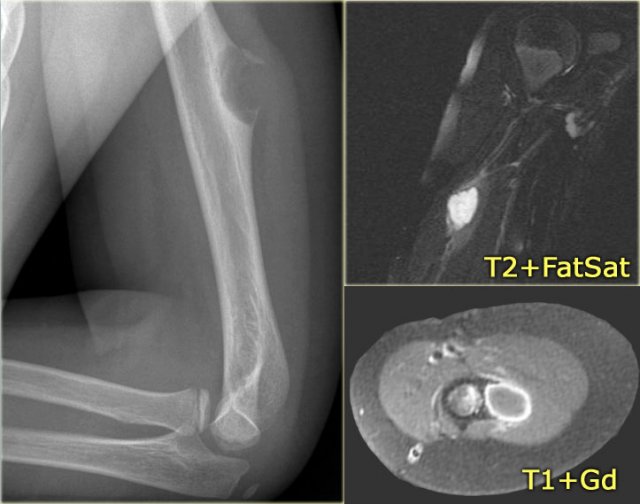

Brown tumor (2)

On the left images of a 30-year-old male with well-defined lytic lesion of the olecranon.

On the radiograph several ridges can be seen and a pathologic fracture (arrow).

The T2-weighted image with fat saturation demonstrates fluid-levels due to sedimentation.

Most likely diagnosis: giant cell tumor and ABC.

Biopsy revealed brown tumor.

Here images of a 33-year old male with a diaphyseal eccentric sharply defined lytic lesion predominantly located in the cortical bone.

CT shows the cortical origin with thin peripheral rim in this patients with hyperparathyroidism.

Diagnosis: Brown tumor.